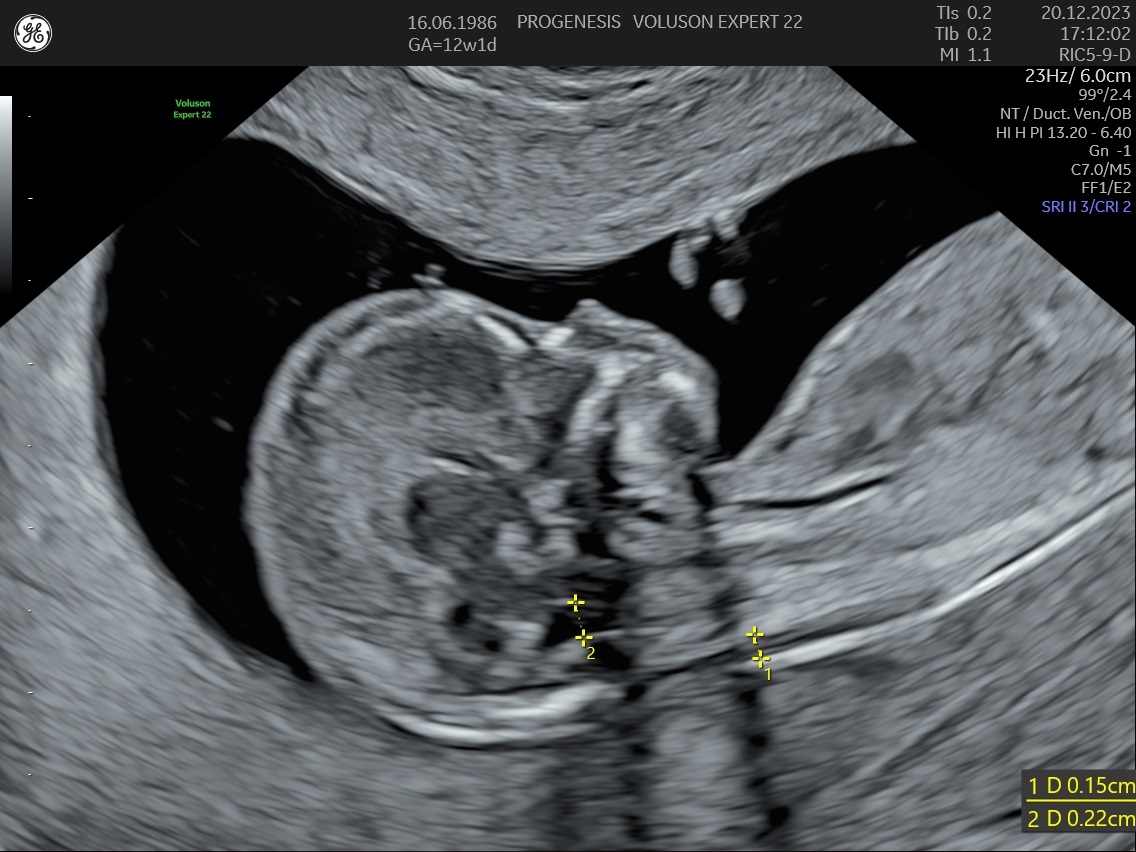

Αξιολόγηση του κινδύνου για το σύνδρομο Down και άλλων χρωμοσωμιακών ανωμαλιών.

Ο κίνδυνος μιας χρωμοσωμιακής ανωμαλίας, είναι ατομικός για κάθε γυναίκα για τη δεδομένη εγκυμοσύνη.

Εξαρτάται από την ηλικία της, το ιστορικό των προηγούμενων κυήσεων, την αξιολόγηση στο έμβρυο υπερηχογραφικών δεικτών όπως, της αυχενικής διαφάνειας, του ρινικού οστού, της ροής στην τριγλώχινα βαλβίδα και το φλεβώδη πόρο, ανατομικές ανωμαλίες που πιθανά να συνδέονται με χρωμοσωμικά/ γενετικά σύνδρομα καθώς και τη μέτρηση τριών ορμονών (PAPP-A, free βHCG και PLGF) στο αίμα της μητέρας.